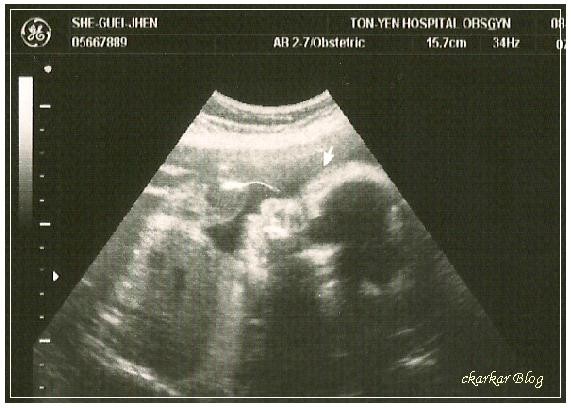

8/19 隔一個月的產檢媽媽體重增加了2公斤多,妹妹體重為1300公克,醫生說有點大!!